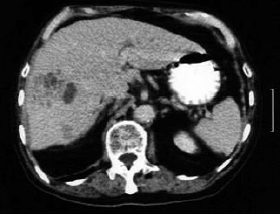

Um homem de 65 anos apresenta febre, astenia, perda de apetite, náusea e emagrecimento há cerca de 3 semanas. Os exames laboratoriais revelaram Htc 30%, Hgb 10g%, Leucócitos 11000 (0 – 0 – 0 – 0 – 7 – 68 – 17 – 8), AST 29 U/L (normal até 31 U/L), ALT 30 (normal até 37 U/L), fosfatase alcalina 320 U/L (normal até 120 U/L), bilirrubina total 0,9 mg/dL, bilirrubina indireta 0,7 mg/dL. USG abdominal: massa heterogênea de limites pouco definidos em lobo direito do fígado. TC de abdômen (a seguir). Observe as imagens e assinale a alternativa que apresenta o diagnóstico provável.